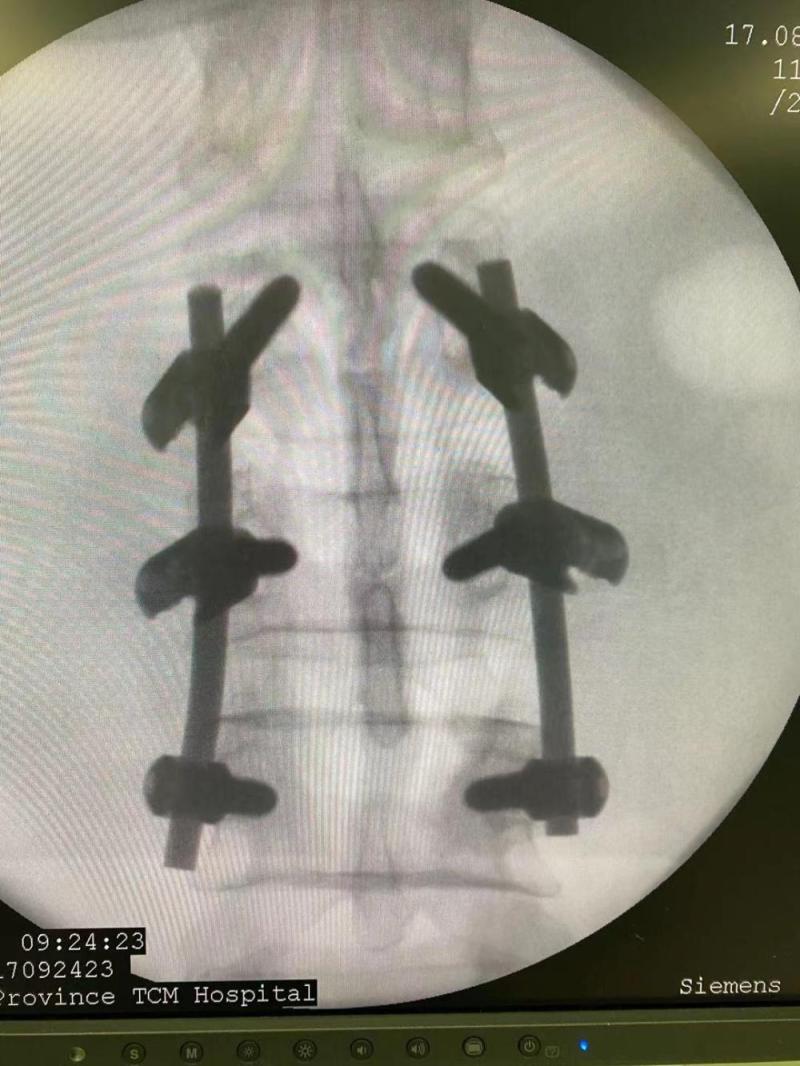

八月十二号回廉江老家,搞卫生,竹梯滑倒,跟着滑倒,腰椎第三节、左脚踝粉碎性骨折,17号做腰椎手术,25号做脚手术。Screenshot_20211119_071742_com.huawei.himovie.jpgScreenshot_20211119_071901_com.huawei.himovie.jpgScreenshot_20211119_071946.jpgScreenshot_20211119_071912_com.huawei.himovie.jpg